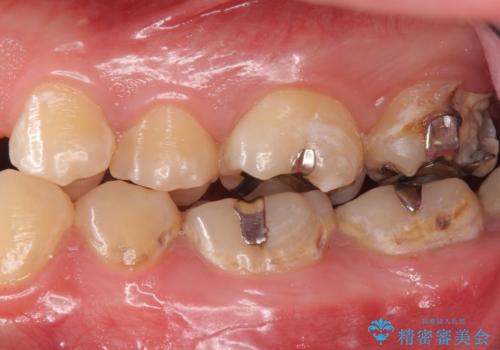

- 奥歯が欠けてしみるとのことで来院された患者様です。

かなり大きな虫歯であることと、清掃不良により歯全体が脱灰していたため、クラウンでの修復処置を行います。

奥に生えている親知らずも清掃不良であったため、今回治療する歯の清掃性を高めるために抜歯を行います。